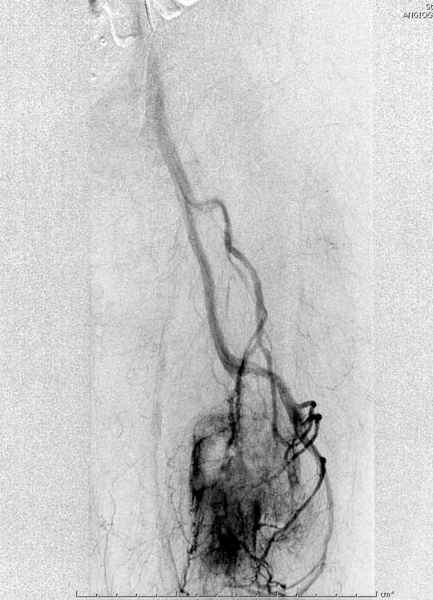

В зависимости от характера опухоли некоторые патологические переломы имеют риск кровотечения во время операции. Множественные литературные данные подтверждают, что надо проявить осторожность при интрамедуллярном остеосинтезе при неизвестных опухолях, особенно где имеется подозрение на Renal Cell Carcinoma. (RCC- hypernephroma) http://www.bonetumor.org/tumors/pages/page64.html

Для предупреждения кровотечения во время рассверливания, за день до операции провели эмболизацию сосудов питающий метастаз. http://radiology.rsnajnls.org/cgi/reprint/150/3/673.pdf (7-11, 12-15-16)